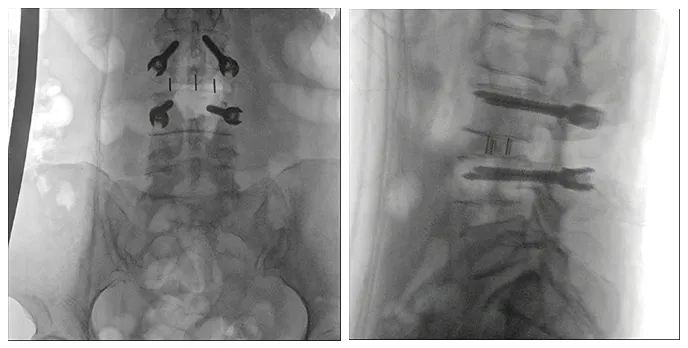

使用普愛醫(yī)療術(shù)中三維導(dǎo)航C臂進行透視,根據(jù)透視影像引導(dǎo)確認責(zé)任間盤、規(guī)劃手術(shù)方案,充分暴露骨組織,并通過專業(yè)器械切除椎板,暴露神經(jīng)及椎管;在C形臂的引導(dǎo)下,確定責(zé)任間盤上下椎體椎弓根位置,制定進針點及進針方向,沿椎弓根方向植入脊柱螺釘進行固定;放入椎間融合器,加固螺釘。最后再進行C形臂透視,確認手術(shù)的完成效果。

手術(shù)效果確認